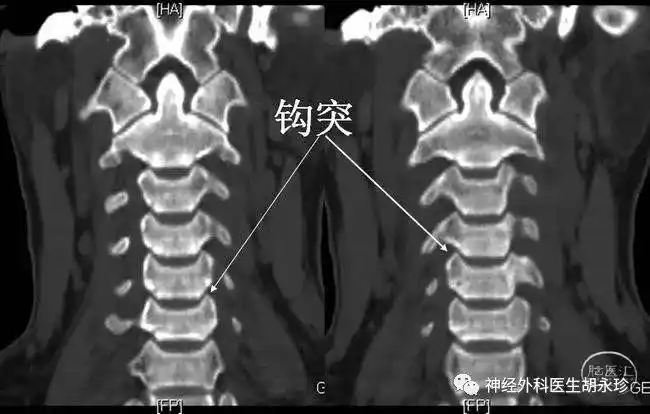

发现观察钩椎关节的最佳角度是颈椎斜位片,且可通过观察钩突骨质增生